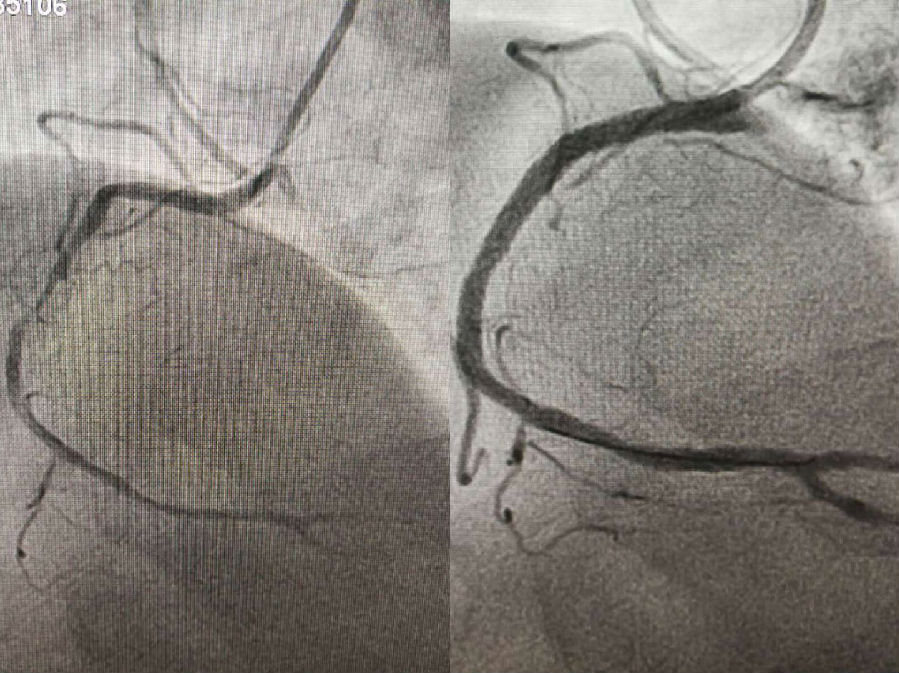

2017年12月17日,在北京阜外醫(yī)院心內(nèi)科冠脈介入中心張洪亮教授的指導(dǎo)下,我院成功為四位冠心病患者實(shí)施了冠狀動(dòng)脈介入治療術(shù)。

手術(shù)由我院心內(nèi)科侯濤主持,趙丁峰操作治療,放射科趙貴生主任和王海申副主任配合,呂懷智副院長(zhǎng)和心內(nèi)科陳彥主任全程監(jiān)控,為其中三位患者成功進(jìn)行了支架植入術(shù)和一例冠狀動(dòng)脈造影術(shù),目前患者均恢復(fù)良好,實(shí)現(xiàn)了不出遠(yuǎn)門(mén),即可在我院接受治療

冠狀動(dòng)脈造影術(shù)是通過(guò)穿刺血管,對(duì)冠狀動(dòng)脈狹窄或閉塞部位進(jìn)行治療,使血管管腔恢復(fù),從而達(dá)到血運(yùn)重建、恢復(fù)心肌供血。此類(lèi)手術(shù)的成功開(kāi)展,對(duì)今后冠狀動(dòng)脈粥樣硬化性心臟病手術(shù)治療的全面開(kāi)展起到了積極的推動(dòng)作用,這也是我院為滿(mǎn)足人民群眾健康需求和促進(jìn)衛(wèi)生事業(yè)更進(jìn)一步發(fā)展,更好地為廣大患者服務(wù)的又一碩果。